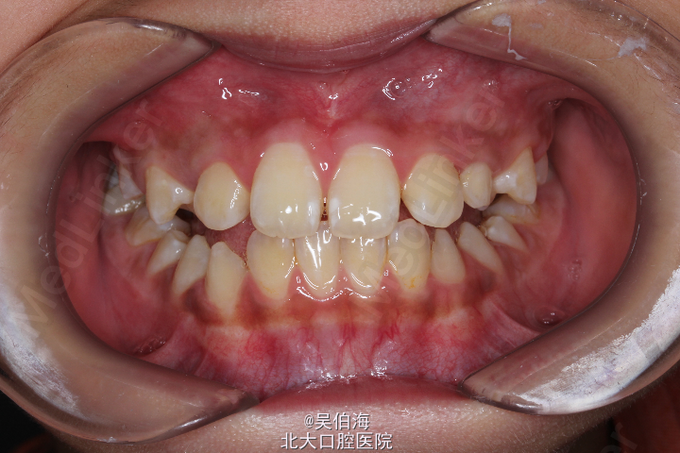

地包天,求治。患儿家长自诉患儿自换牙以来有地包天,自觉影响美观,来院求治疗。

双侧三类磨牙关系,前牙反覆合反覆盖。能后退至切对切。有抿上唇的不良习惯。

安氏三类(假性) 第一期佩戴Frank三功能矫治器纠正前牙反合,择期行第二期固定矫治。

患儿每日佩戴大于14小时,数月后地包天得到矫正,效果良好